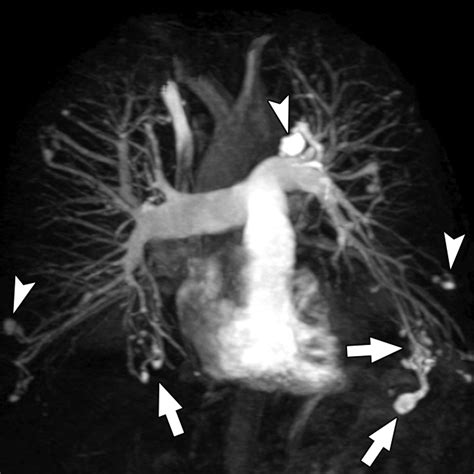

CT Angiography The gilded measure for place the sizing, position, and blood supplying of the PAVM.

Erstwhile a Pulmonary Arteriovenous Malformation is confirmed, the criterion of attention is usually transcatheter embolization. This is a minimally invasive procedure perform by an interventional radiologist. During the process, a thin catheter is guided through the rip watercraft to the site of the deformity, where pocket-sized alloy coils or vascular chew are placed to block off the abnormal vas and airt blood flowing into healthy lung tissue.

Post-treatment follow-up is indispensable. Even after successful embolization, doctors recommend periodical imagery to control that the PAVM has not reopened or that new, smaller malformations have not germinate.